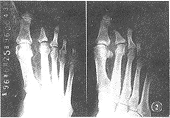

例1:男,64岁。糖尿病8年,右足溃疡5个月,治疗不愈。X线表现:右足普遍骨质稀疏,第5趾骨破坏,隐约可见少许骨性关节面影,第3~5

骨远端不同程度破坏(图1)。

图1 右足骨质稀疏,3~5

骨,第5趾骨有骨质破坏